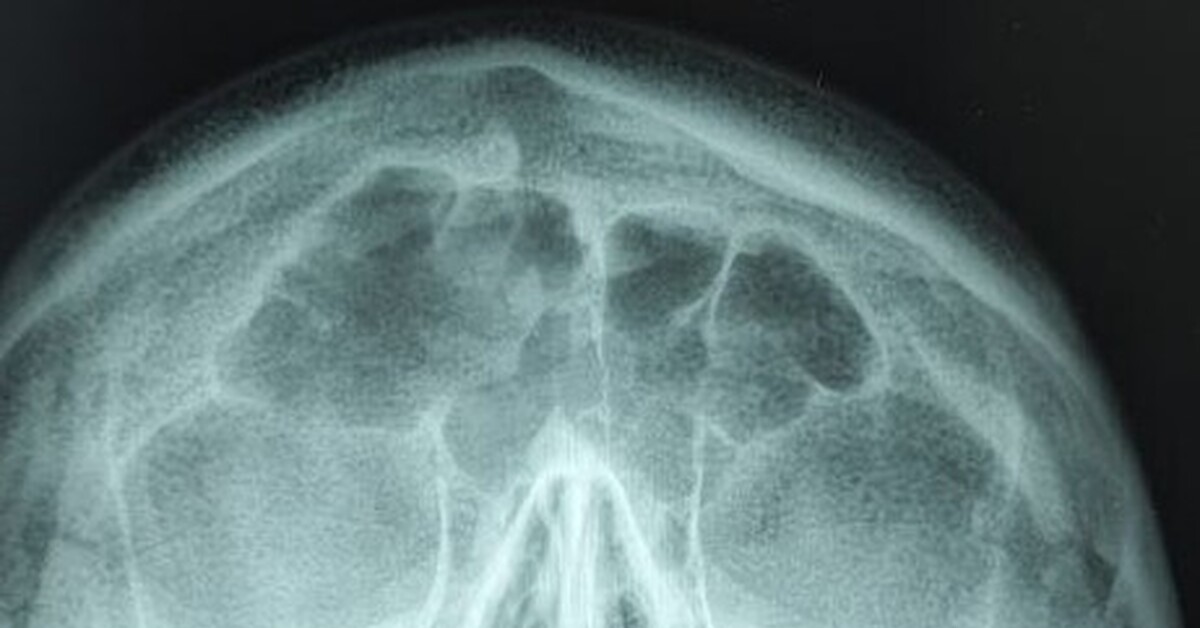

Киста В Голове Фото

Киста В Голове Фото 146 фотографий